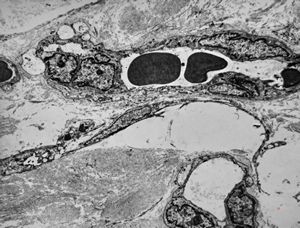

F,42y. | pseudoangiomatous hyperplasia

F,42y. | pseudoangiomatous hyperplasia

F,42y. | pseudoangiomatous hyperplasia

F,42y. | pseudoangiomatous hyperplasia

F,42y. | pseudoangiomatous hyperplasia